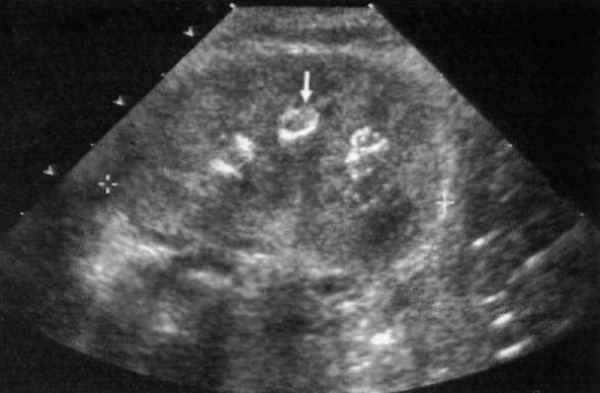

Операция STING проводится путем цистоскопии, при этом проводят субуретеральное введение в зону устья мочеточника тефлона или другого биологически инертного вещества с целью устранения везико-уретерального рефлюкса. УЗИ демонстрирует внутри задней стенки мочевого пузыря эхогенное возвышение (фото 3). Если характерный бугорок (возвышение) не определяется, это свидетельствует о неудачном проведении операции, поскольку введенный материал переместился. Иногда он может смещаться вверх к почке: при этом он визуализируется как эхогенное образование в просвете собирающей системы и дает заднее затенение.

Фото 3. Мочевой пузырь. Ультразвуковое изображение мочевого пузыря в поперечной проекции у ребенка дошкольного возраста после операции STING: стрелкой обозначен характерное возвышение